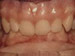

Missing lateral incisors